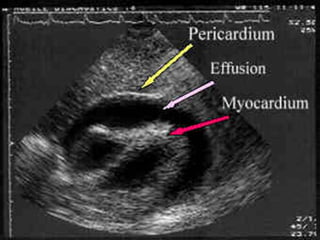

Primary Survey - Circulation

• Cardiac Tamponade can cause hypotension

with little blood loss.

• Becks triad: hypotension, distended neck

veins, muffled heart sounds

• Easily confirmed with ultrasound

• Pericardiocentesis

• Pericardial Window.

Primary Survey -Circulation • Cardiac Tamponade can cause hypotension with little blood loss. • Becks triad: hypotension, distended neck veins, muffled heart sounds • Easily confirmed with ultrasound • Pericardiocentesis • Pericardial Window.